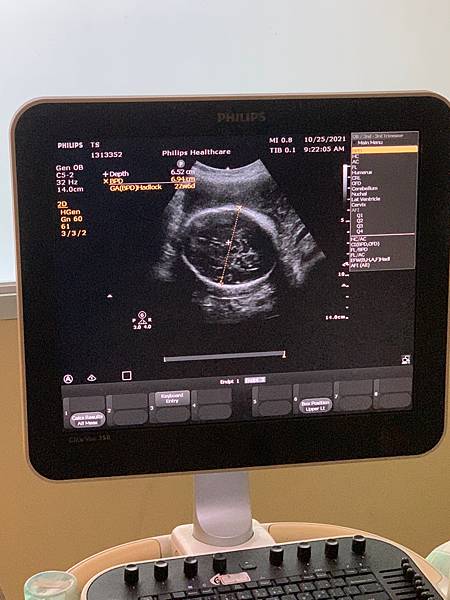

上週做完高層次之後,接著就是23週的產檢了。

因為上次做完高層次之後,寶寶狀況都很好,但是就是臍帶繞頸讓人有點擔心,所以這週回診的時候也會比較想知道寶寶有沒有繞回來。